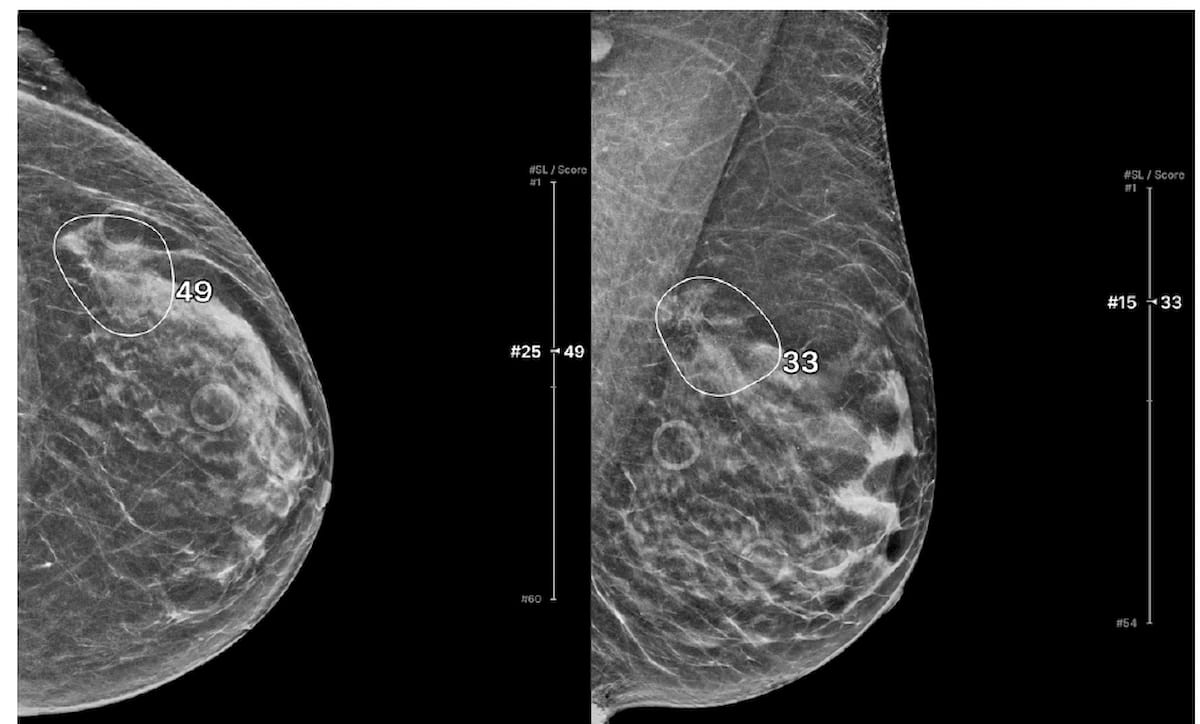

A proposed alternative to a previously validated deep learning neural network for assessing short-term breast cancer risk, the emerging AsymMirai deep learning mammography-based model showed comparable breast cancer risk prediction with an emphasis on bilateral dissimilarity, according to new research.